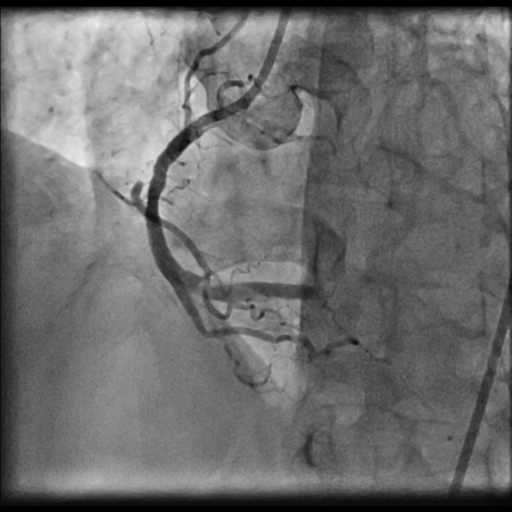

LMCA was engaged with JL 4.0 7 Fr. catheter. First septal collateral was used to reach the distal cap of the lesion using Sion black, Runthrough extrafloppy and Fielder XT-R wire with microcatheter but could not penetrate the distal cap. The lesion could not be crossed with Gaia second and Gladius¢ç Mongo¢ç wire. Antegrade approach was decided to a cross the lesion with Gaia second wire. Antegrade approach caused a dissection resulting in a sub intimal hematoma which extended into the Posterolateral branch. This dissection and the hematoma straightened the vessel near the distal cap. Now this straightening allowed the ASAHI Gladius¢ç Mongo¢ç wire to cross the distal cap retrogradely. The Gladius¢ç Mongo¢ç wire could not be positioned into the true lumen. Now to avoid further dissection proximally the Mongo wire was exchanged with Pilot 150 wire. This wire could cross the proximal cap and finally into the guide catheter. Pilot 150 wire was exchanged with Choice Floppy LS 300 cm which was externalized. A finecross microcatheter was advanced over this wire antegradely. Retrograde microcatheter removed and rest of the case was completed via antegrade approach over Runthrough NS Floppy wire. Lesion was predilated with 2.5x12 mm NC balloon @ 12 atm. Promus Elite 2.75x38 mm DES deployed in mid to distal RCA @ 12 atm. An overlapping stent Xience Xpedition 3.0x28 mm DES deployed from ostium to mid RCA @ 11 atm. Post dilatation with 3.25x10 mm NC balloon @ 11 atm. Distal TIMI III flow achieved.

PTCA 3.mp4